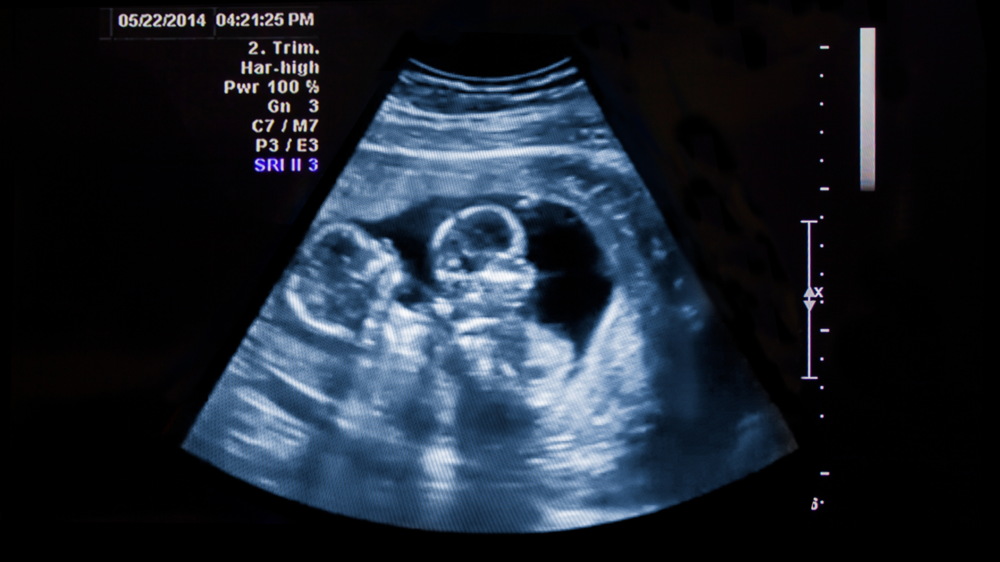

twin pregnancy

You may require more scans if there is more than one baby. These regular ultrasounds allow your doctor to see how each baby is growing up close and ensure they are both getting the food they need.

The good thing is that any differences in growth can be spotted early, and your doctor can step in if needed. Hearing about extra scans may sound overwhelming, but many moms find comfort in seeing their babies more often and watching their growth step by step.